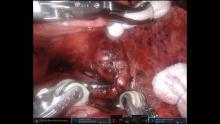

Completely Pre-Operative Planned Robotic Right S3 Segmentectomy, Assisted by 3D Reconstruction [1]

This video shows a right S3 segmentectomy completely planned and preoperatively assisted by 3D reconstruction imaging. This model can also be used intraoperatively to assist the surgery and dissection planes in order to increase patient safety and adequate resection margins.